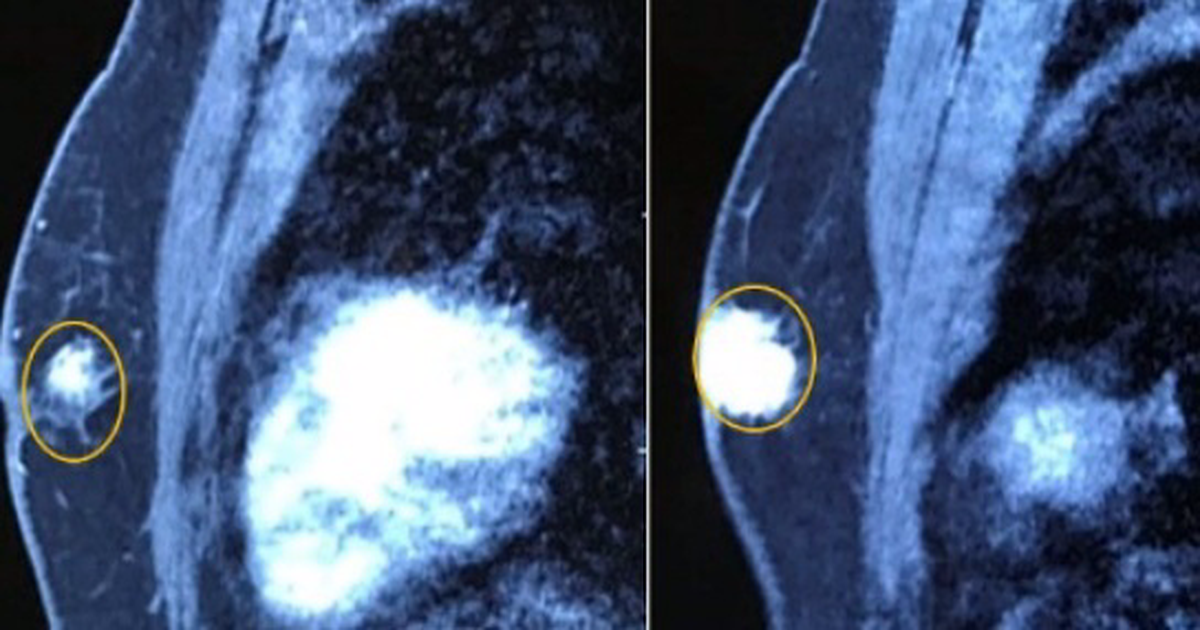

Tuyến vú trái có khối u kích thước 2×2,5cm, chắc, ranh giới không rõ, còn di động.

Người đàn ông mắc căn bệnh tưởng chỉ có ở phụ nữ - 1

Hình ảnh chụp cộng hưởng từ tuyến vú có khối u ngay dưới núm vú trái kích thước 21x28mm, chưa xâm lấn cơ thành ngực, co kéo núm vú (Ảnh: B.V).

Bệnh nhân được chỉ định cắt toàn bộ tuyến vú trái, vét hạch. Sau hậu phẫu bệnh nhân ổn định sẽ tiếp tục điều trị các liệu pháp toàn thân (hóa trị, nội tiết…) kết hợp với điều trị và theo dõi bệnh lý về tim mạch.